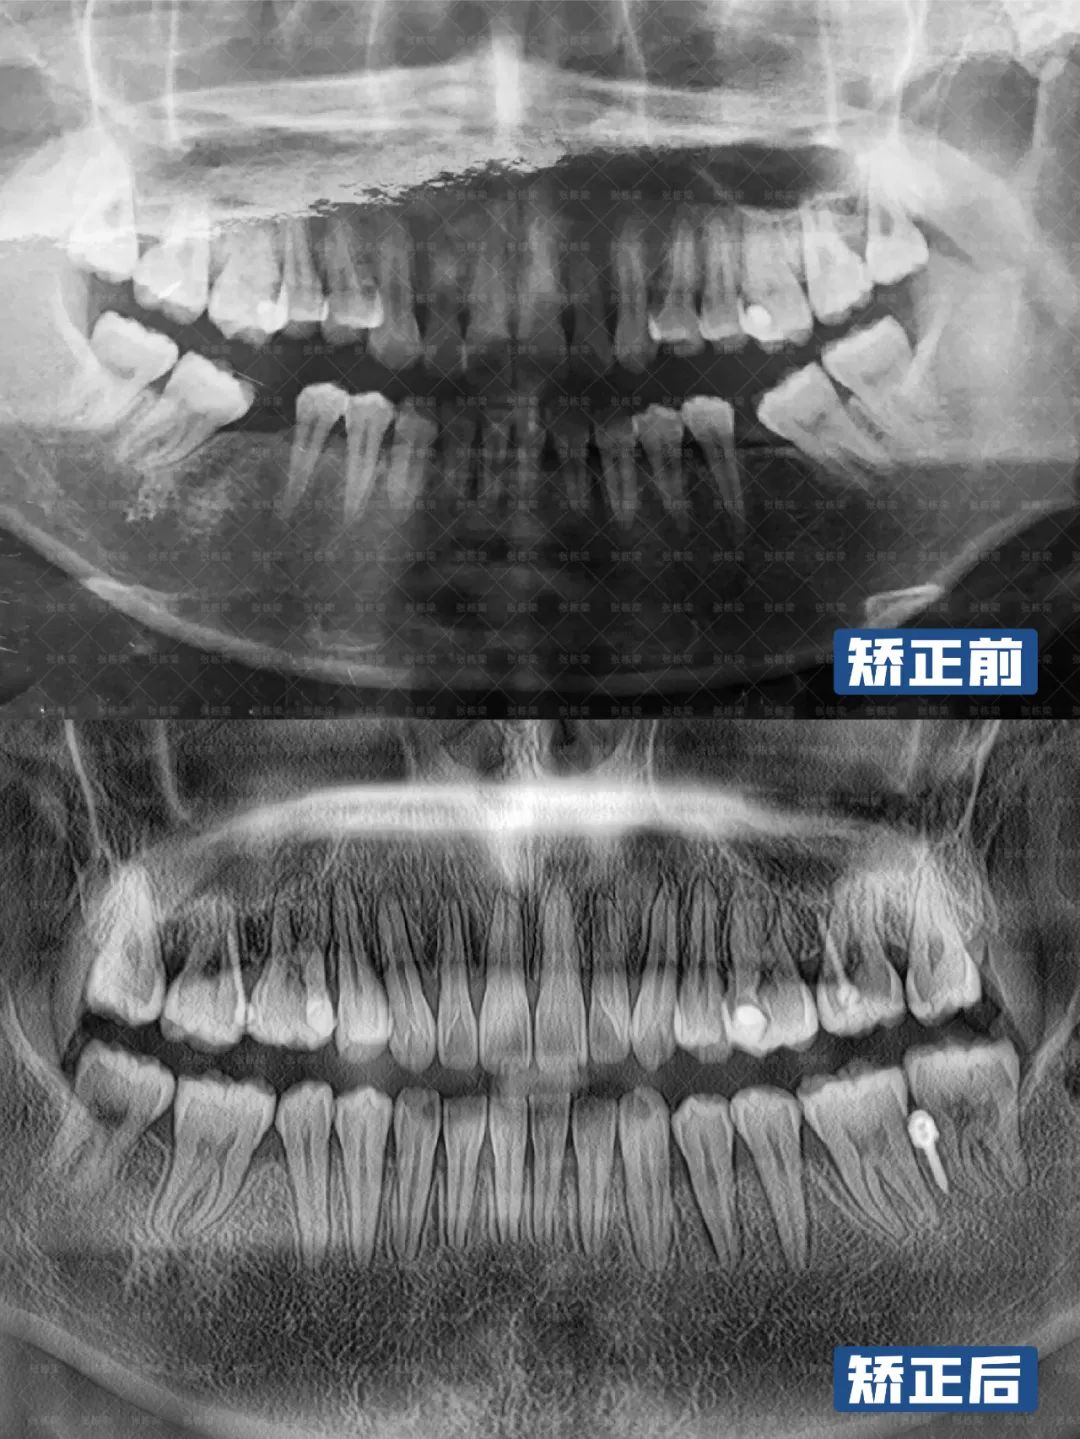

综合牙片面型分析:

1、正面观:面部双侧基本对称,面下1/3高度稍长,放松时开唇露齿,闭嘴时颏肌紧张,唇肌无力;2、侧面观:高角,凸面型,上颌前突,颏部后缩,颌平面倾斜;6、牙列:恒牙列,上下前牙唇倾,上牙弓尖圆形,牙弓狭窄,下颌双侧6缺失,下颌双侧7、8近中倾斜,上下牙弓不匹配;

牙齿矫正可见:

上下前牙转矩角度正常,牙齿排齐,中线对齐,深覆盖解除,颏部形态前伸,上下牙弓匹配,前牙达到正常覆合覆盖,牙齿尖窝关系良好。

从健康角度来看,牙齿和咬合都恢复良好。从美观角度来看,凸面型改善良好,颏肌紧张、开唇露齿都有了好的改善,收获正常的下巴。